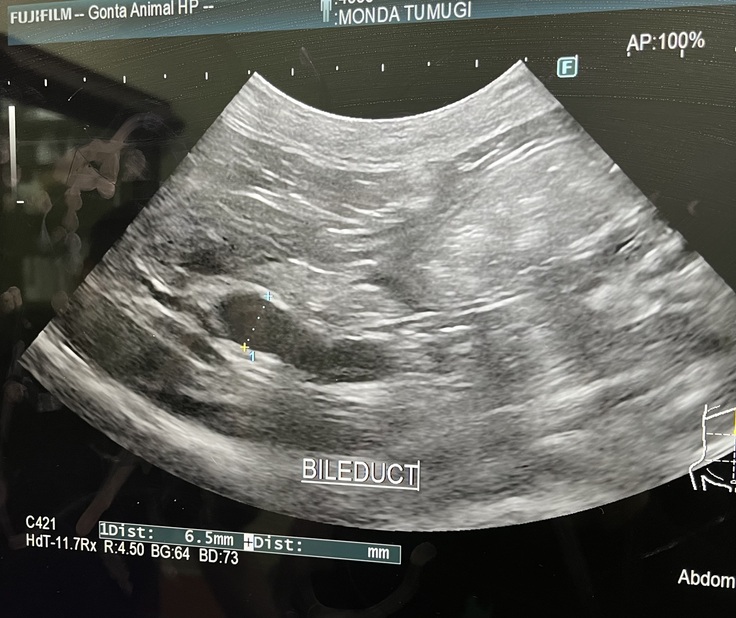

エコーも再度行いましたが、胆管には問題はなく、腎臓に水疱が見つかるという

結果となりました。

エコー写真です。